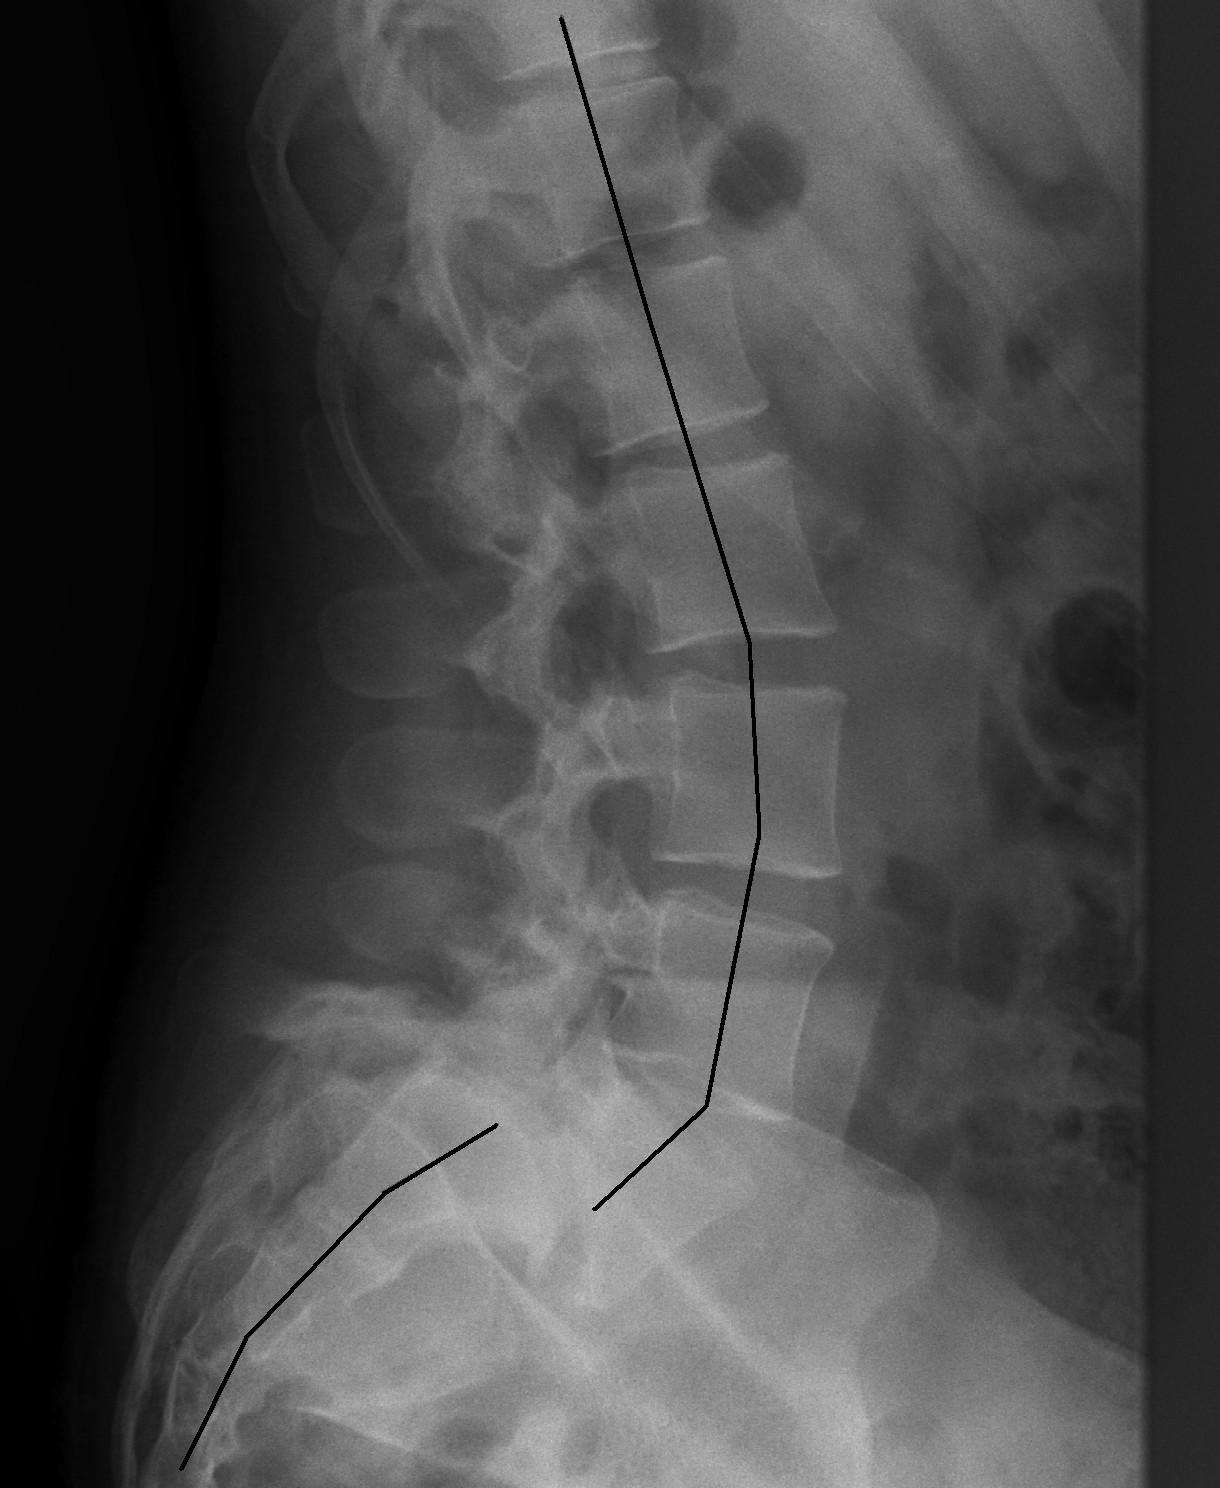

- Standing lumbar spine X-ray (lateral view)

- Shows the presence and degree of vertebral slip, helps estimate the grade.

- Flexion and extension X-rays

- Helps assess whether the segment appears to move more than expected (instability), which can influence management decisions.

Grading / Classification

- Meyerding Grade I

- 0% to 25% slip. Often managed well with spondylolisthesis physiotherapy exercises and load modification.

- Meyerding Grade II

- 25% to 50% slip. Management depends on symptoms, stability, and nerve involvement.

- Meyerding Grade III

- 50% to 75% slip. Higher likelihood of ongoing symptoms; needs careful physiotherapy-led rehab and sometimes specialist input.

- Meyerding Grade IV

- 75% to 100% slip. More complex, with greater risk of nerve involvement and postural changes.

- Meyerding Grade V (spondyloptosis)

- Greater than 100% slip. Rare, typically specialist-managed.